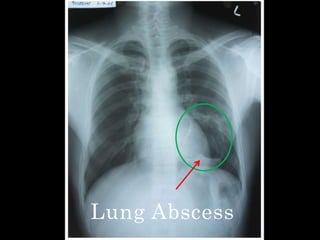

Lung Abscess

   Loculated cavity with thin wall(maybe post

infective cyst, wall made up of a fibrous

tissue)

   Presence of air fluid level

   Mild trachea shift to the left(probably due

to rotation)

   Fundic air bubbles separately seen

Lung abscess  Loculated cavity with thin wall(maybe post infective cyst, wall made up of a fibrous tissue)  Presence of air fluid level  Mild trachea shift to the left(probably due to rotation)  Fundic air bubbles separately seen